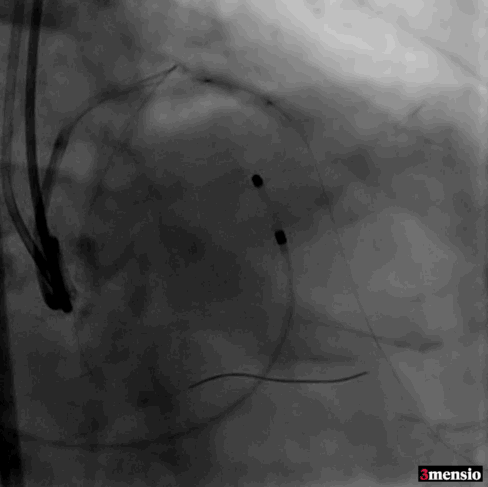

根部造影

跨瓣

20mm球囊预扩

标准位释放定位

23mm球囊后扩

术后造影

瓣膜定位精准,标准位释放,轻微瓣周漏,术后效果良好,手术取得圆满成功。